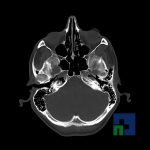

În cazul traumatismelor cranio-cerebrale:

- Evaluarea deplasării liniei mediane

- Evaluarea cisternelor perimezencefalice

- Diagnosticul edemului cerebral, a contuziei cerebrale, a leziunilor axonale difuze edematoase/hemoragice, a dilacerării cerebrale, a hematomului intraparenchimatos posttraumatic, a hematoamelor subdurale/extradurale (acute, subacute, cronice), a hemoragiei intraventriculare, a hemoragiei subarahnoidiene

- Diagnosticul traumatismelor de bază de craniu

- Diagnosticul fistulei LCR

- Diagnosticul herniilor cerebrale